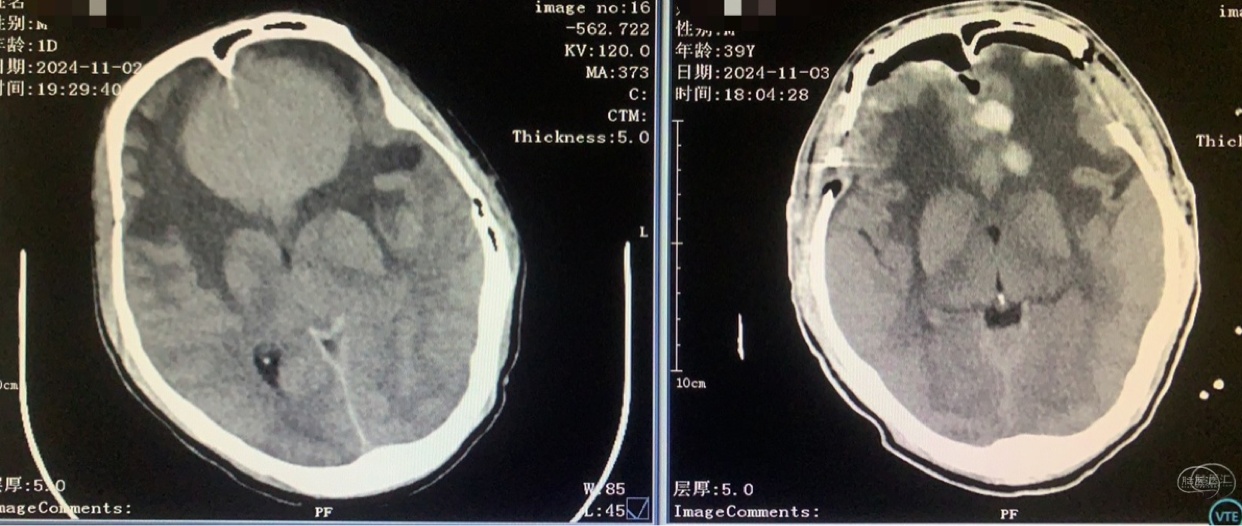

术前CT

双侧入路计划(为降低优势半球损伤风险先右侧处理,实在不好搞再左侧)

从右额分块切除处理大部分后,因条件所限单侧入路风险高遂加开左侧额外侧(骨窗较右侧小)。

术前术后对比